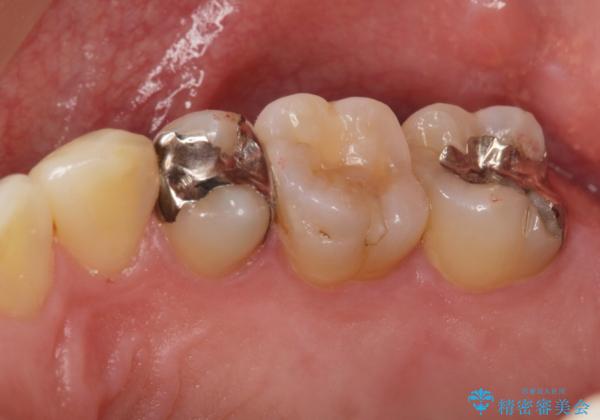

奥歯の詰め物のやりかえ セラミックインレー、ゴールドインレー

- 上の奥歯の詰め物が合っていないため、やりかえを行いました。

- 20万円 内訳 左上56:emaxインレー7万円x2 、左上7:PGAインレー6万円 (税別)費用は治療当時の料金となります

上の一番奥の歯は、一番目立たない場所なので(他人から見えない)、ゴールドインレーでも目立ちません。

セラミックインレーでは割れやすい大きさの虫歯または、歯が薄くなって被せなければいけないような場合でも、金属(ゴールド)は耐久性があり、クラウン(被せ物)にしなくて済みます。